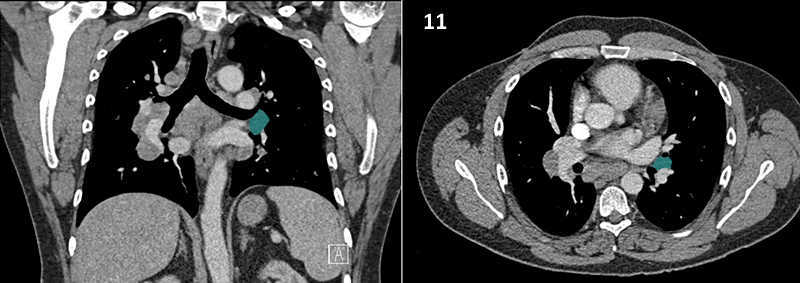

Nodal zones and stations according to the International Association for the Study of Lung Cancer (IASLC) node map.

Table (above): Nodal zones and stations according to the International Association for the Study of Lung Cancer (IASLC) node map. (Source: 1,2) *Depends on the side of the tumour.